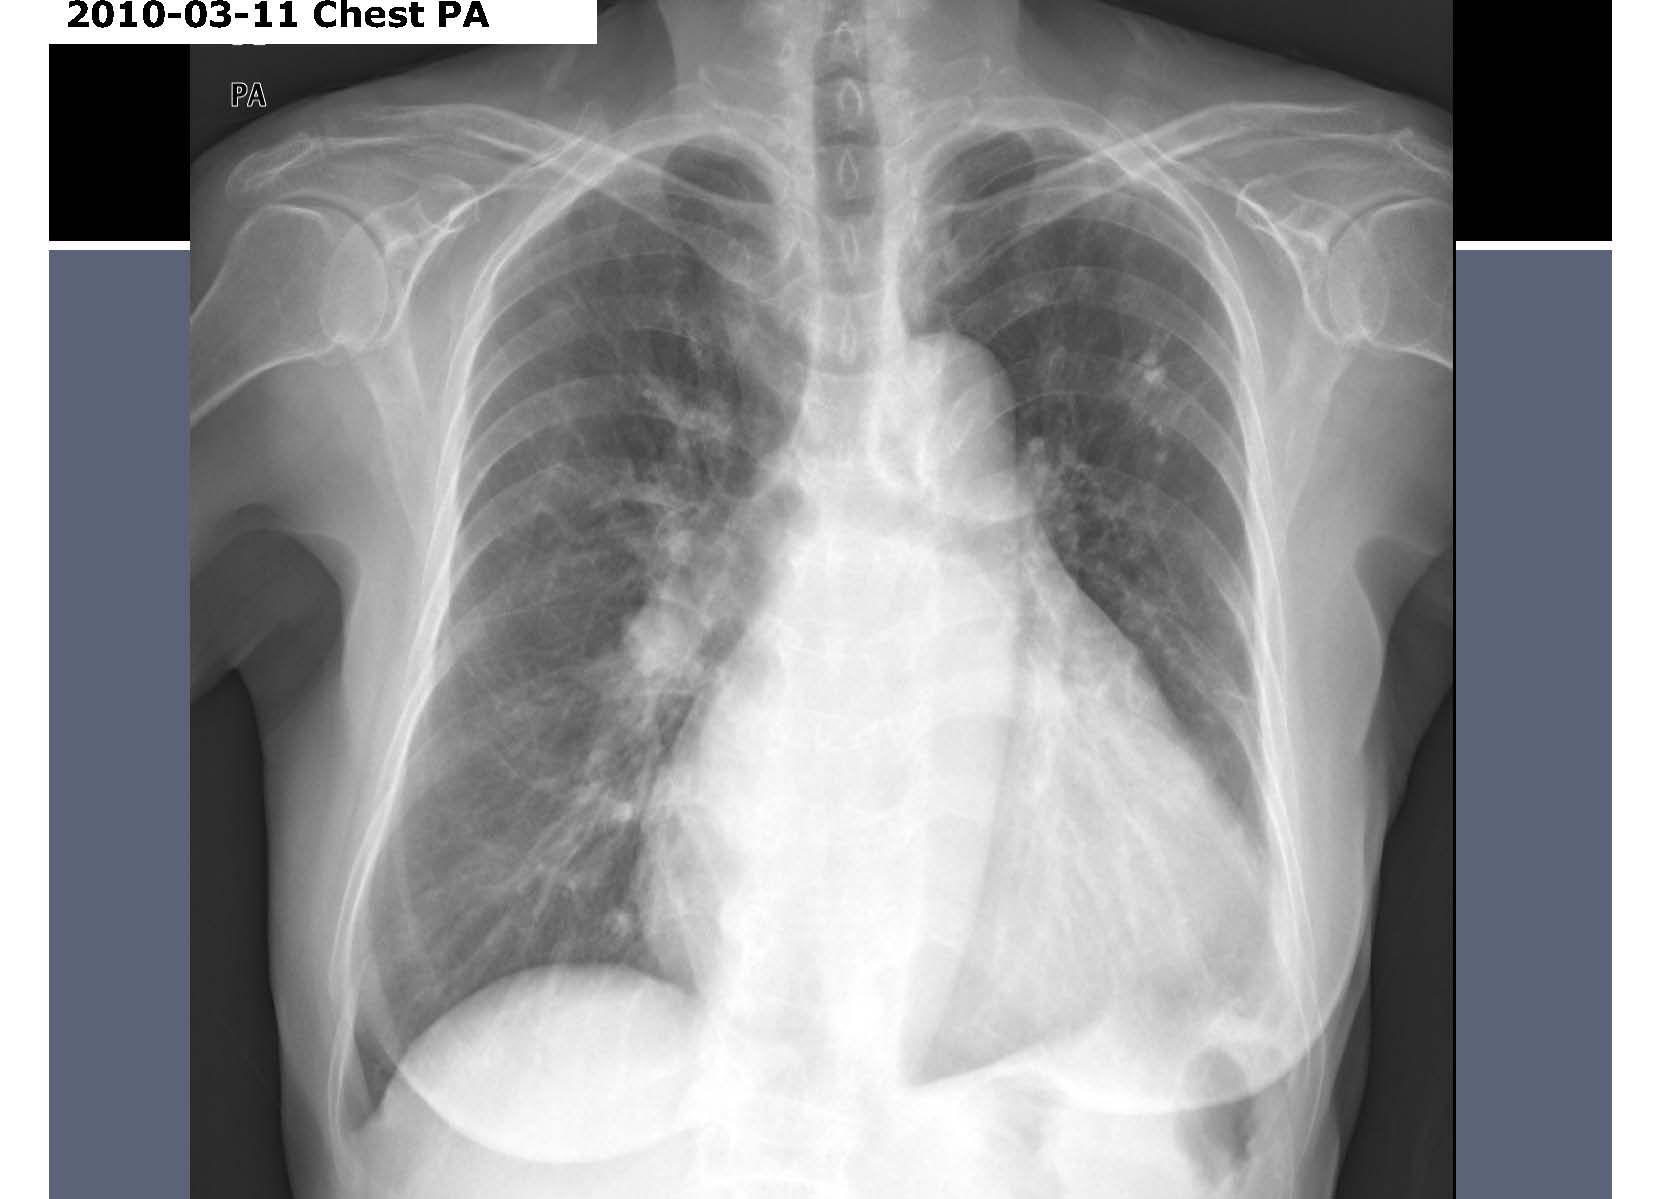

F/54, C.C: Abnormal chest x-ray

Jin Hur, Yonsei university, Severance Hospital

HIT : 63